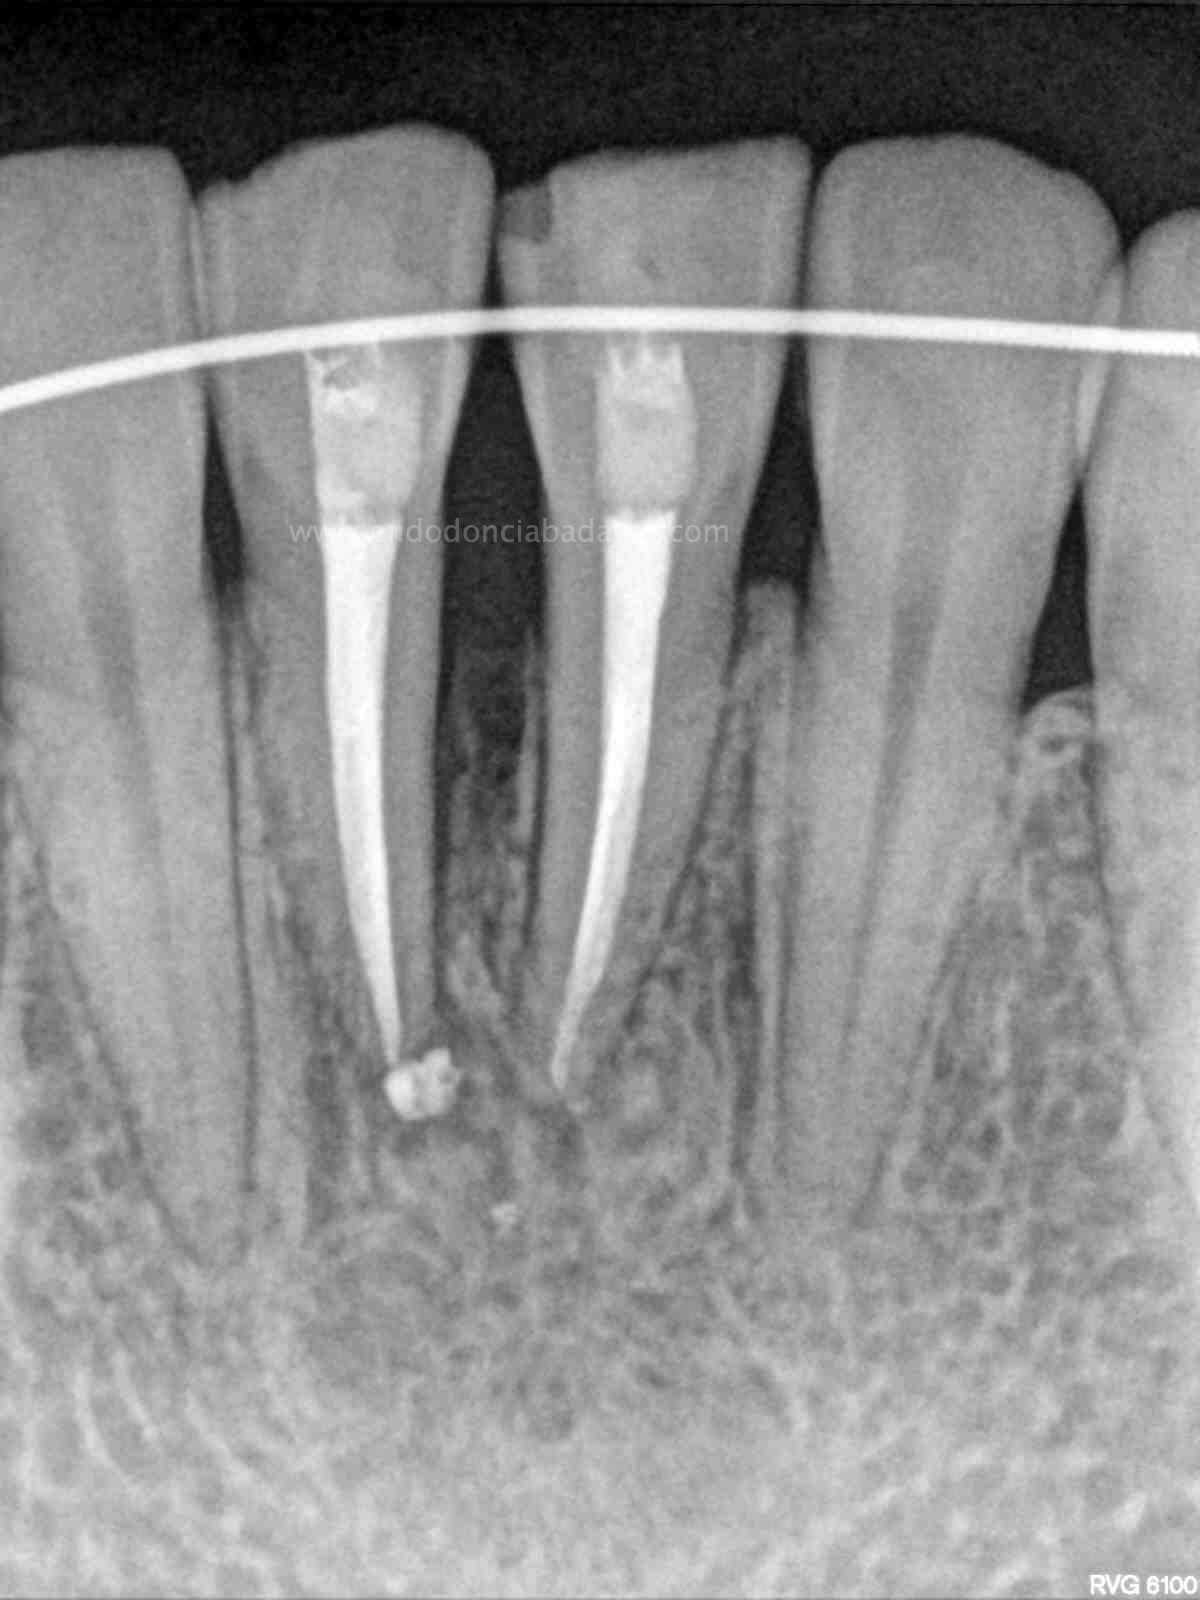

En una segunda sesión, obturamos los conductos tridimensionalmente, conductos acintados. Usaríamos la técnica de Ola continua de Buchanan haciendo un backfilling con la Pistola ObturaII: